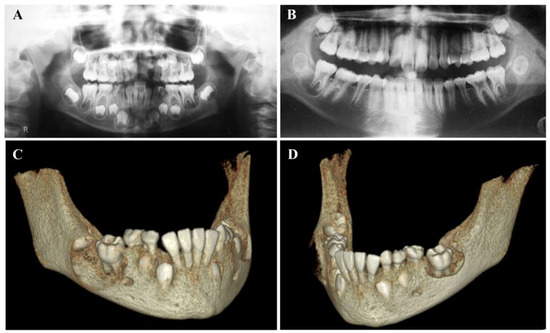

4.1. Buccal Bifurcation Cyst

4.1.2. Radiographic Features